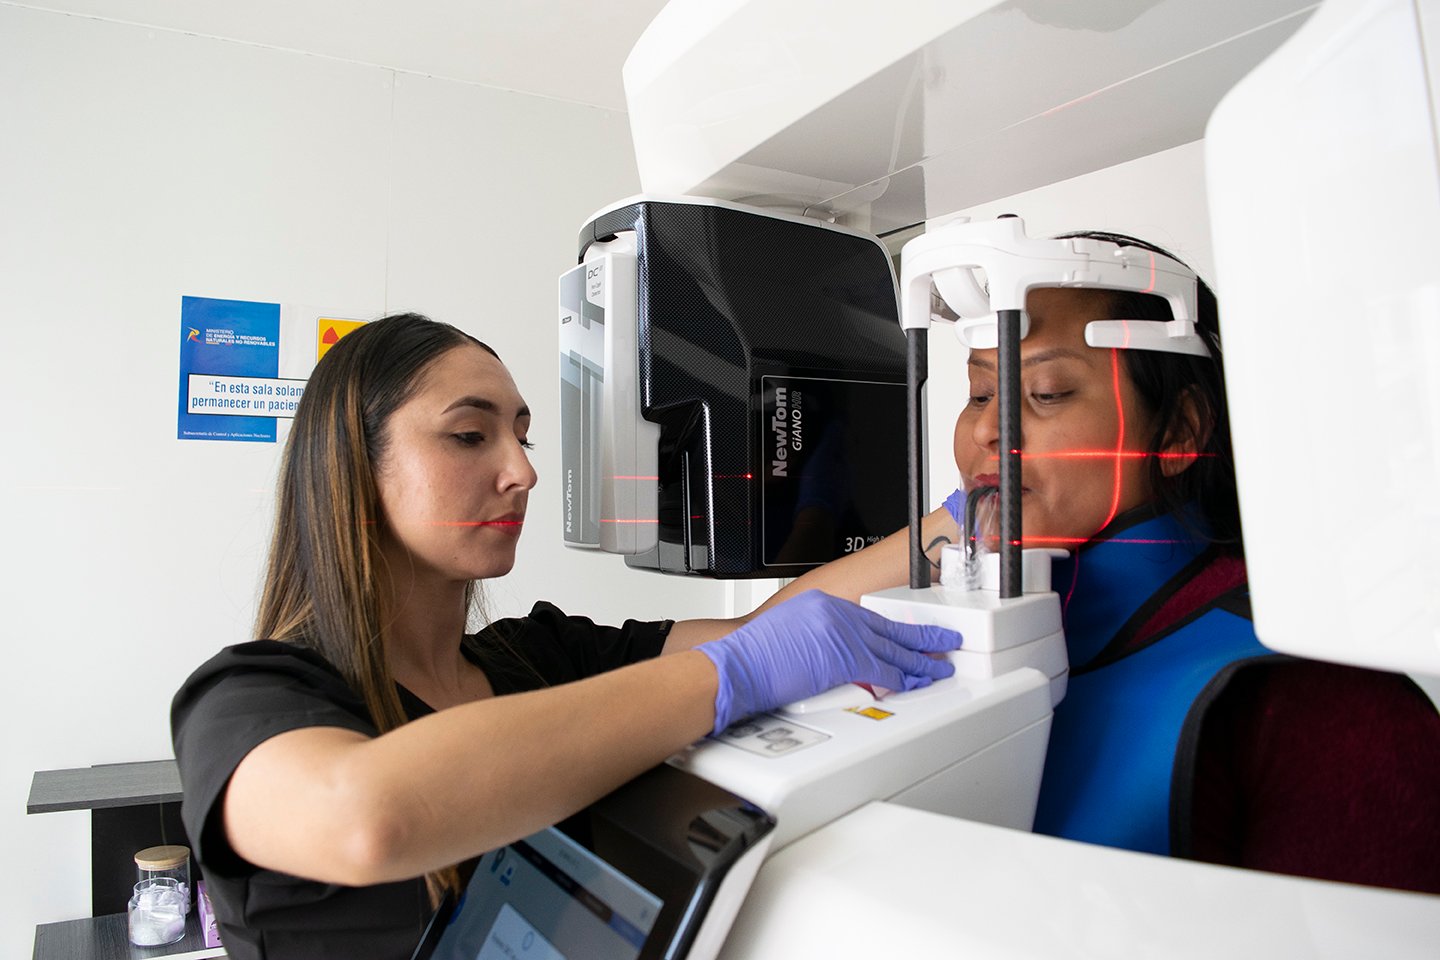

La tomografía computarizada dental maxilar es una técnica de imagen avanzada que permite obtener imágenes tridimensionales de la estructura maxilofacial. A diferencia de las radiografías convencionales, que ofrecen una visión bidimensional, la tomografía computarizada proporciona una representación más detallada y precisa de los huesos, dientes y tejidos blandos de la región maxilar. Este tipo de exploración utiliza rayos X para crear cortes transversales del área, que luego se procesan mediante un software especializado para generar imágenes volumétricas.

Esta tecnología ha revolucionado la forma en que los dentistas y cirujanos maxilofaciales evalúan y diagnostican condiciones dentales. La tomografía computarizada dental maxilar se ha convertido en una herramienta esencial en la odontología moderna. Su capacidad para visualizar estructuras complejas permite a los profesionales de la salud dental identificar problemas que podrían pasar desapercibidos con métodos de imagen más tradicionales.

Una de las principales ventajas de la tomografía computarizada en la salud dental maxilar es su capacidad para proporcionar imágenes de alta resolución y precisión. Esto permite a los dentistas observar detalles minuciosos de la anatomía dental y maxilofacial, lo que resulta fundamental para un diagnóstico certero. Por ejemplo, en el caso de pacientes que requieren implantes dentales, la tomografía computarizada puede revelar la densidad ósea y la ubicación exacta de los nervios, lo que ayuda a evitar complicaciones durante el procedimiento.

Otra ventaja significativa es la reducción de la exposición a radiación en comparación con las tomografías computarizadas convencionales. Las técnicas modernas han sido diseñadas para minimizar la dosis de radiación sin comprometer la calidad de las imágenes. Esto es especialmente importante en odontología, donde muchos pacientes son niños o personas que requieren múltiples estudios a lo largo del tiempo.

La seguridad del paciente es una prioridad, y la tomografía computarizada dental maxilar se presenta como una opción eficaz y segura.